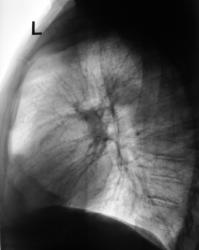

При расшифровке флюорограграмм (2007) пациент был "взят на контроль" - на уровне 4 ребра слева обнаружена крупноочаговая тень.

Провели рентгенографию в прямой стандартной проекции. С учетом "неубедительности" теневой картины "решили понаблюдать".

2008 г. Пациент "взят на контроль"

Зафиксировано увеличение тени в размерах. Произведена рентгенография в прямой стандартной проекции.

Было высказано предположение о наличии "маленького периферического рака", зафиксирована "линзеподобная тень" паракостально. Пациент направлен на консультацию в онкологический диспансер.